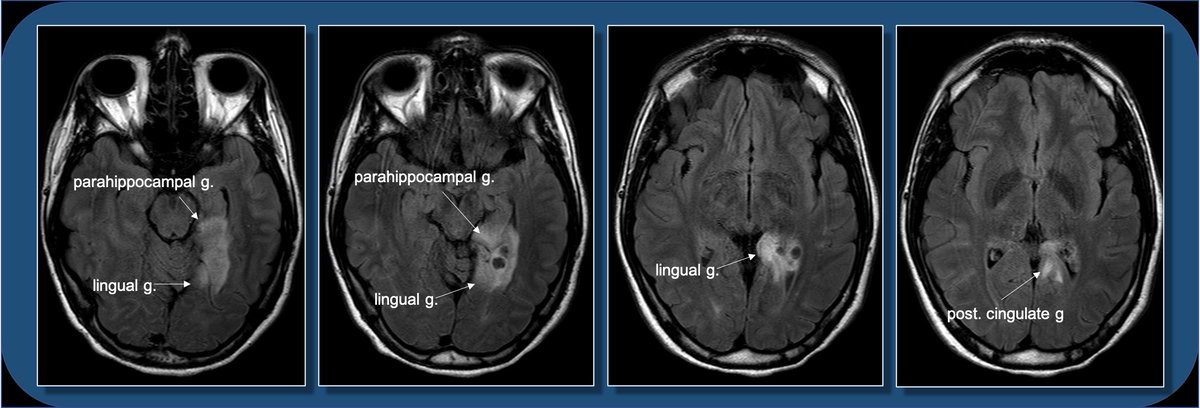

This location can be a bit difficult to describe if you aren’t up on gyral anatomy. Is it med temporal lobe? occipital lobe? limbic? Describing gyral location is more precise, can explain expected symptoms, and clue in future surgical approach.

Gyral anatomy of inf occipitotemporal surface: The inf. temp. gyrus wraps from lateral https://abs.twimg.com/emoji/v2/... draggable="false" alt="➡️" title="Pfeil nach rechts" aria-label="Emoji: Pfeil nach rechts">inferior. The fusiform and lingual gyri span from occipital lobe posteriorly to temporal lobe anteriorly. Parahippocampal is medial temporal (anterior continuation of the lingual g).

Gyral anatomy of the medial brain surface: calcarine sulcus divides the cuneus from lingual gyrus at the med occ lobe. The lingual g continues anteriorly along the med/ inferior temporal lobe. The cingulate g wraps sup & posterior to corpus callosum along the medial brain.

The lingual gyrus is involved in holistic visual and word processing, encoding visual memories, imagery, and dreaming. The ganglioglioma in the shown case is centered in the lingual gyrus.

Fusiform g is just lateral to lingual g on the inf surface of temporal lobe, separated by collateral sulcus. It& #39;s medial to the ITG, separated by ITS. Involved in face and body recognition; word form recognition (on left). (Fusiform g was not definitively involved by tumor). 9/13

Parahippocampal g. is anterior continuation of lingual g. Part of Limbic System. Important in memory encoding and retrieval, visual and social contextualizing.

Cingulate g. is part of the limbic circuit; the post cingulate cortex (PCC) is important in default mode network, awareness, pain, and episodic memory retrieval. PCC including the retrosplenial cortex (which together some call restrosplenial gyrus) is involved by the tumor. 11/13